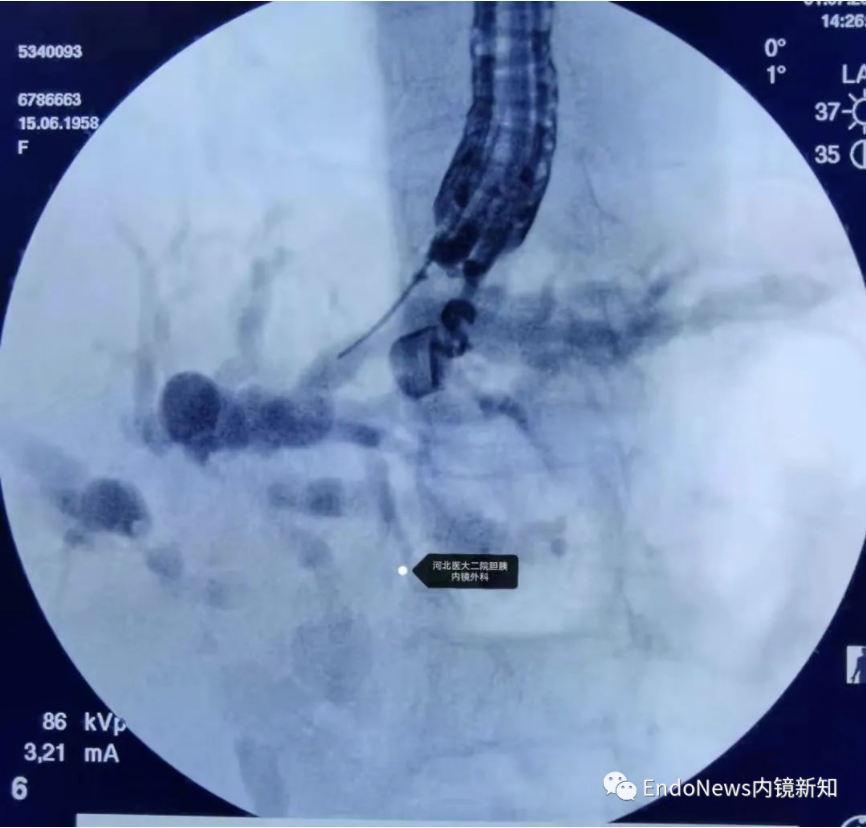

在下面肝内胆管结石的病例所示,这是一个进肝右叶管之后顺行放置双猪尾支架,在二期手术时将窦道扩开,用字母镜液电碎石,再在右侧肝内胆管管进行取石的病例。

病例2:胆肠吻合口狭窄并右侧肝内胆管结石。

HGS造瘘,再碎石取石,置入双猪尾支架

在这个病例中,倘若是左肝管穿刺的第二段或第三段有结石,操作则更为困难,因此不同的病例还需要具体情况具体分析。